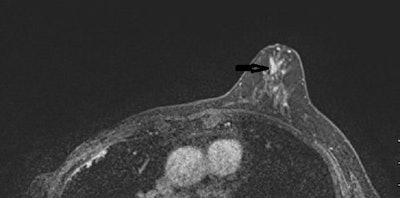

MRI axial plane after injection with fat saturation (above, arrows) and subtraction (below) shows a large nonmass micronodular enhancement with segmental distribution in the inner left quadrants. Mastectomy: 130-mm ductal carcinoma in situ with microinvasion. Images courtesy of Dr. Martine Boisserie-Lacroix and European Radiology.The authors considered all lesions requiring excision found on pathology (papilloma, atypia, nipple adenomatosis, or cancer) as positive results, and they viewed spontaneous resolution of the discharge at one year as a negative result.